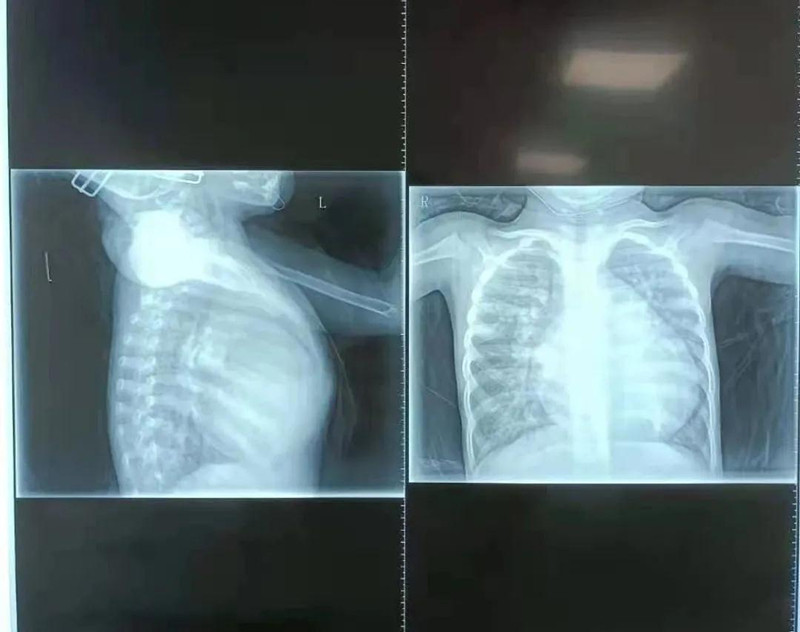

在德州扑克游戏网 小儿心脏病诊疗中心,杨明远医生初见馨馨印象极为深刻,4岁的孩子体重仅10.5公斤,由于心脏变大,她的胸骨被挤压得明显向前凸起。检查发现,馨馨心脏室间隔有直径17mm的缺损,导致左心室血液一部分流向右心室。同时,馨馨出生后动脉导管就未闭合,导致血液从主动脉分流到肺动脉。为了维持全身用血,左心室需要不断增加“劳动量”,而全身血液加上分流到右心室的血液最终都回到左心室,造成左心室严重增大,左室疏末径达到50.1mm,比正常成年人(正常成人左室疏末径为35-50mm)还要大。杨明远医生说,在先天性心脏病中,室间隔缺损比较常见,但像馨馨的心脏畸形严重到如此程度、对身体影响如此大的实属少见。